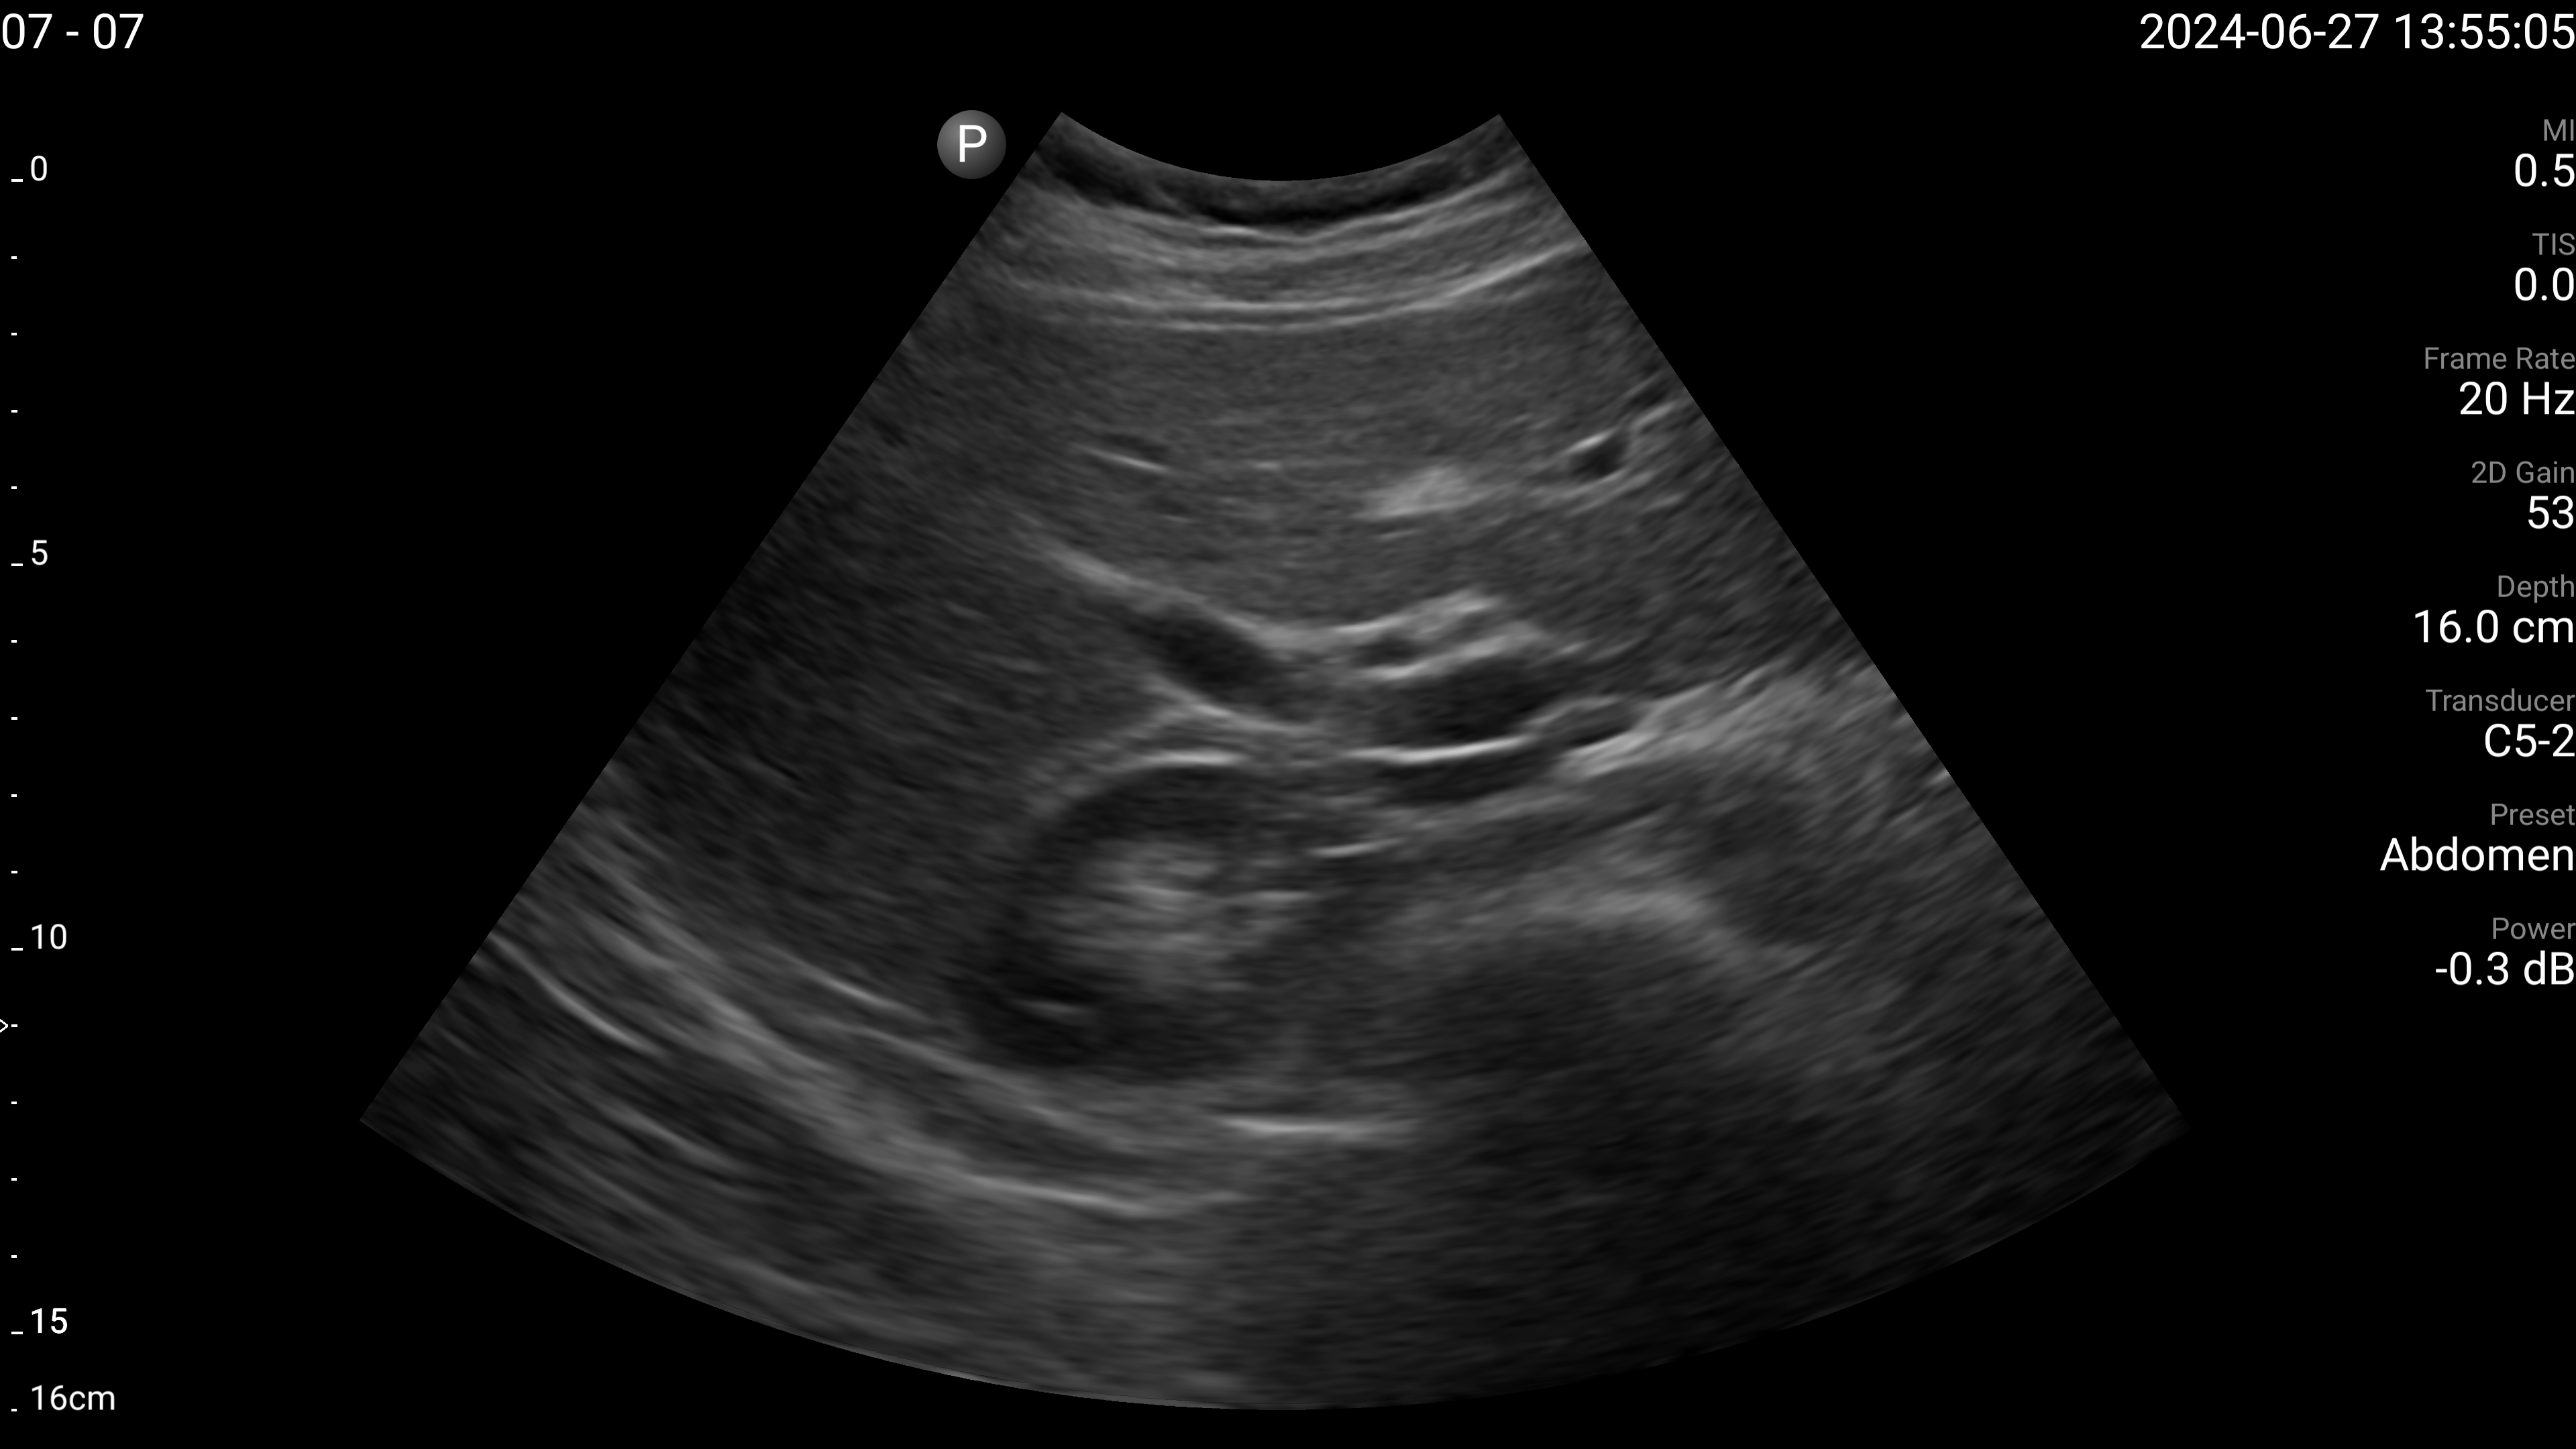

Refer to caption

(c) Left lobe of liver - long axis.

Figure 4: Examples of the target US images acquired by the sonographers using the human teleoperation system.

The sonographers completed 11 abdominal US scans, each with 5 target images and measurements for a total of 55 images. An example image of each of the targets acquired during these tests is shown in Fig. 4. After completing the scans, two radiologists scored the images based on quality, including identifying targets that could not be seen or were not captured (which were given a score of 0). The distribution of these scores is illustrated in Fig. 5. The first radiologist identified 4 out of the 55 targets as not visible, while the second radiologist identified 6 out of 55 as not visible. Combined, this accounted for 7 unique targets that at least one radiologist considered missing. Of these missing targets, three were not captured due to large amounts of bowel gas and body habitus while one was seen but the sonographer did not capture and save the image. When excluding all the missing targets, the images obtained a mean score of 4.28±0.95plus-or-minus4.280.954.28\pm 0.95 out of 5 and 91.7% of the images were scored 3 or higher by both radiologists. A score of 3 or higher indicated the image quality was sufficient for basic image interpretation. 31.3% of the images were scored 5 by both radiologists, indicating the image quality was good and meaningful image interpretation was easy.